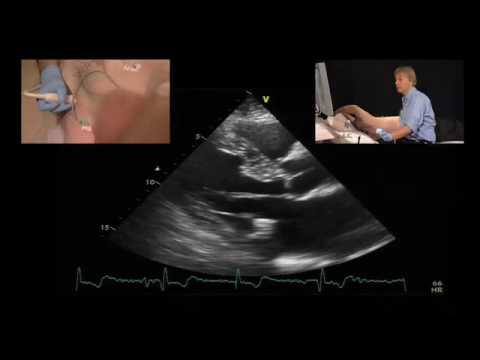

• Mass